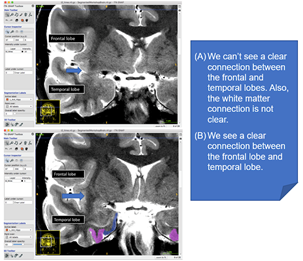

This key landmark will determine where you start drawing the entorhinal cortex. To find this landmark, look for the limen insulae. This is a band of grey matter that joins the frontal lobe to the temporal lobe. It is often easier to visualize on a T1-weighted scan. The two examples below compare a slice in which limen insulae is not visible, versus one that it is clearly visible: